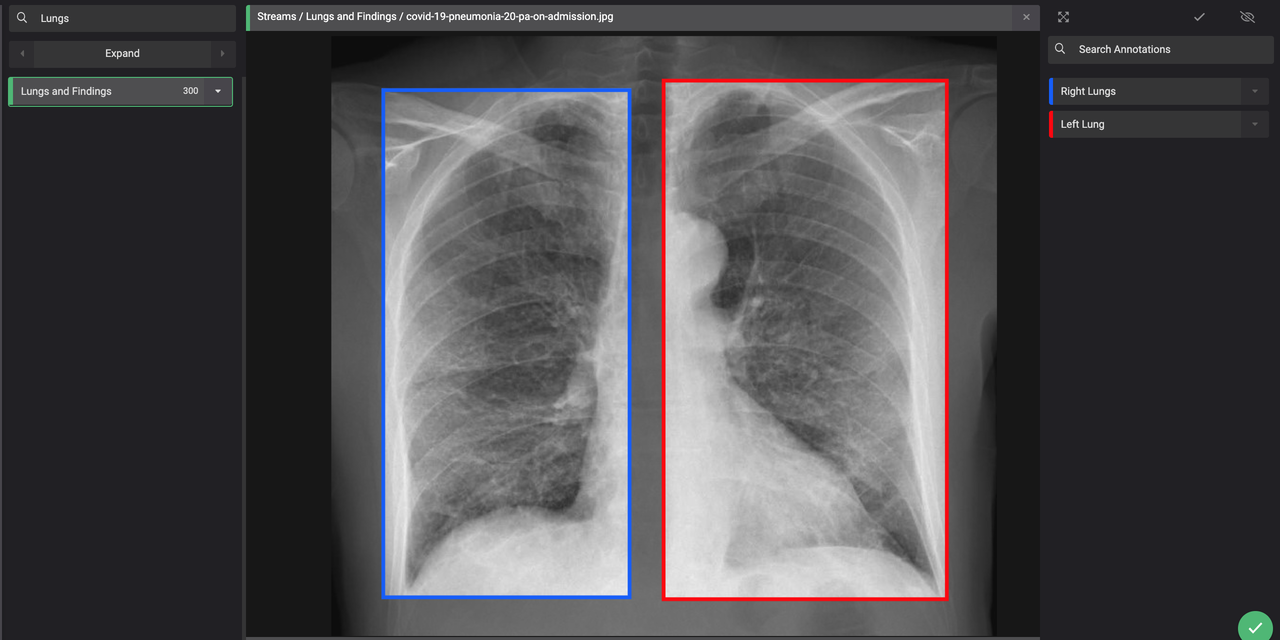

Github Ieee8023 Covid Chestxray Dataset We Are Building An Open Database Of Covid 19 Cases With Chest X Ray Or Ct Images

Finding Rib Fractures On Chest Xray

Chest X Ray Images Pneumonia Kaggle

Chest Xray Images Github Topics Github